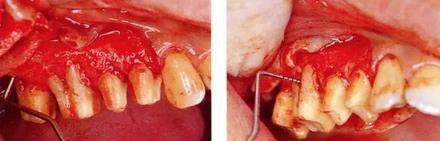

▼圖16-1 ▼圖16-2

圖16-1 對(duì)右上6.7分叉部病變處理時(shí),對(duì)包括右上4.5進(jìn)行齦瓣分割,確認(rèn)骨缺失狀態(tài)。右上7頰側(cè)存在著12mm的骨緣下缺失。

圖16-2 右上6水平的分叉部病變到達(dá)了III度。